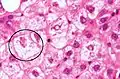

A small quantity of tissue is sampled from the liver when doing a biopsy, which is then examined under a microscope

Micrograph of non-alcoholic fatty liver disease, demonstrating marked steatosis (fat in liver cells appears white; connective tissue, blue). Trichrome stain

A liver biopsy (tissue examination) is the only test widely accepted (gold standard) as definitively diagnosing and distinguishing NAFLD (including NAFL and NASH) from other forms of liver disease and can be used to assess the severity of the inflammation and resultant fibrosis. However, since most people affected by NAFLD are likely to be asymptomatic, liver biopsy presents too high a risk for routine diagnosis, so other methods are preferred, such as liver ultrasonography or liver MRI. For young people, guidelines recommend liver ultrasonography, but biopsy remains the best evidence.[4][6][62][26] Liver biopsy is also the gold standard to detect hepatic fibrosis and assess its progression.[65] Routine liver function blood tests are not sensitive enough to detect MAFLD, and biopsy is the only procedure that can reliably differentiate NAFL from NASH.[15]